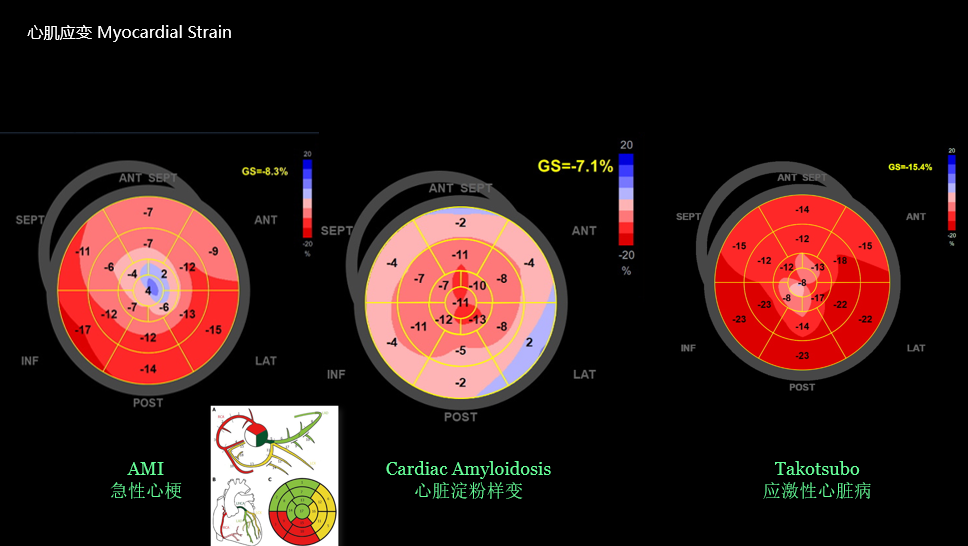

心肌应变:运用斑点追踪自动分析心肌运动形变,精准量化局部收缩/舒张功能,突破传统超声限制,早期发现亚临床心脏病变.

心肌应变成像